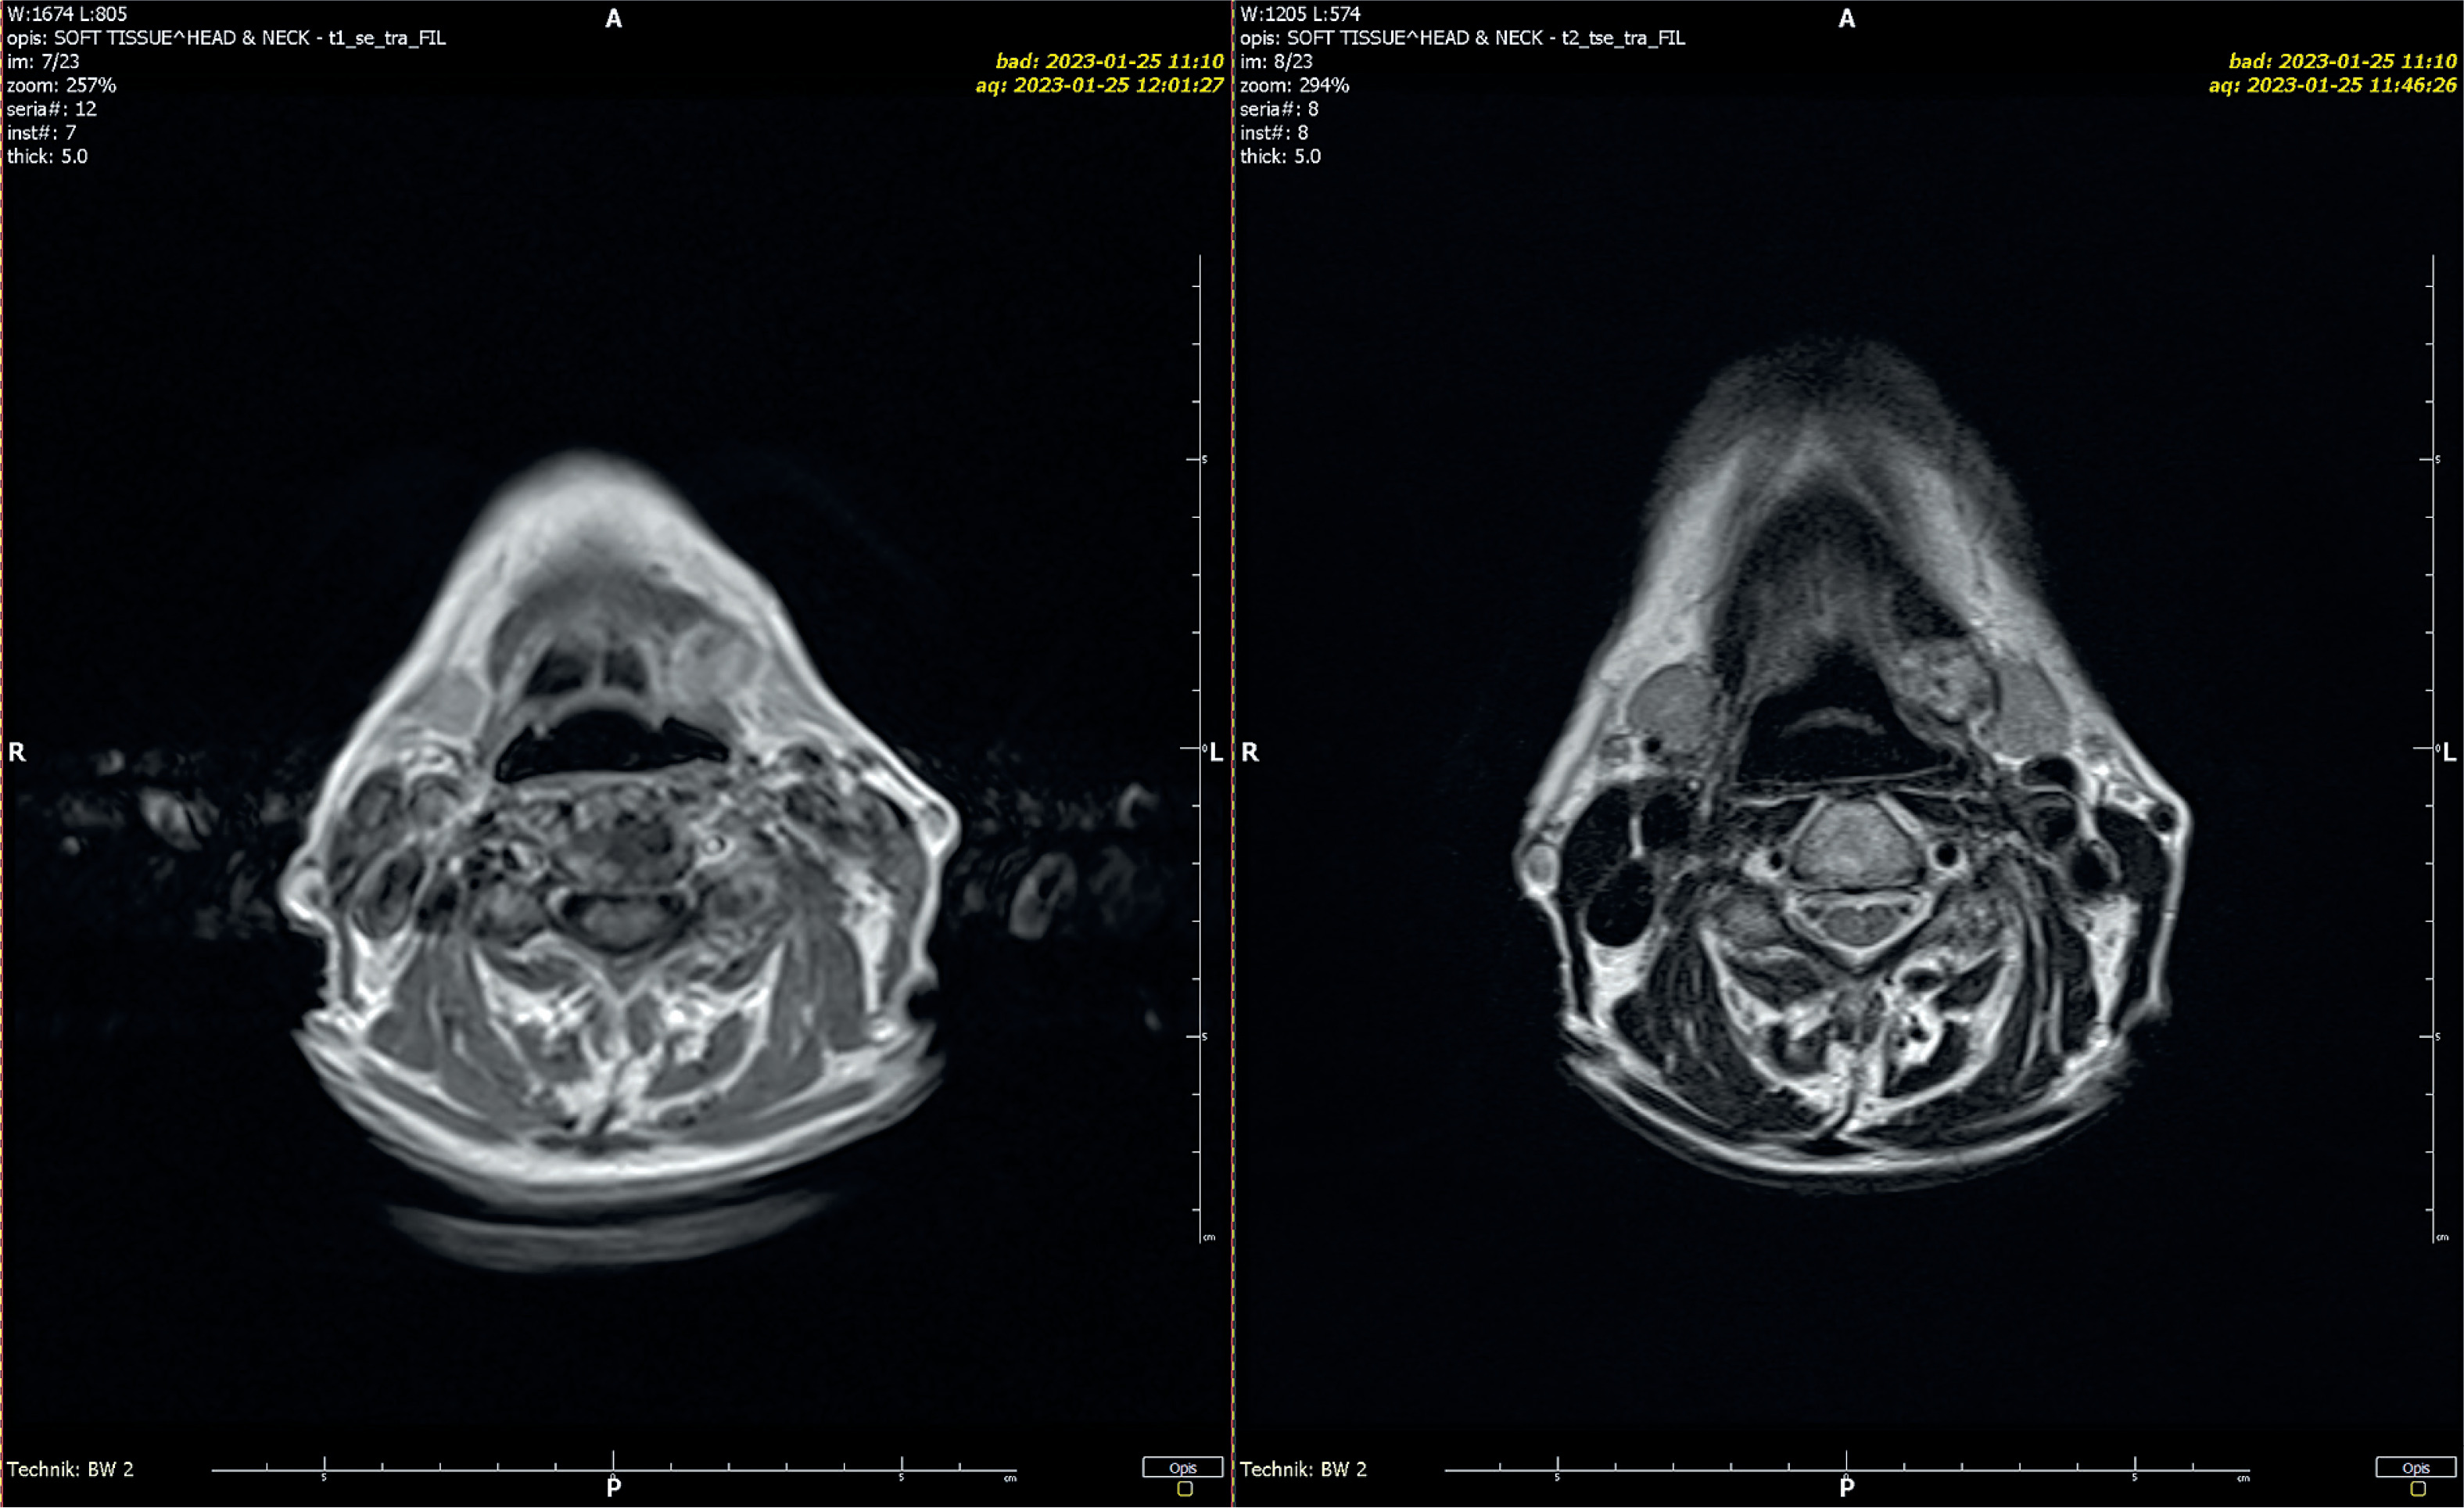

A 72-year-old female patient was admitted to the Dermatology Department due to sudden onset of widespread rash and the eruption of primary, sterile, macroscopically visible pustules on non-acral skin following a recent neurosurgical procedure. The patient’s condition was complicated by elevated inflammatory markers (white blood cells (WBC) = 12.79 × 10³/µl, C-reactive protein (CRP) = 27.7 mg/dl) and decreased levels of both total (7.96 mg/dl) and ionized calcium (0.87 mmol/l), as revealed by laboratory tests. The patient had a history of generalized pustular psoriasis with periods of remission and exacerbation. Based on the clinical presentation of the skin lesions, medical history, additional test results, and the diagnostic criteria established in 2017 by the European Rare and Severe Psoriasis Expert Network (ERASPEN) (which include primary sterile pustules visible on non-acral skin, systemic inflammation, and a recurrent disease course), an exacerbation of GPP was diagnosed. Given the severity and progression of the skin lesions, as well as the patient’s overall deteriorated condition, a comprehensive treatment approach was initiated. Based on the clinical status, drug availability, and expert recommendations, treatment with acitretin and glucocorticosteroids was introduced. Acitretin was administered at an initial dose of 20 mg/day (0.5 mg/kg), and methylprednisolone at 8 mg/day. A rapid and favorable clinical response was observed, with marked reduction of pustular lesions. However, on the fifth day of pharmacotherapy, the patient developed notable bilateral swelling in the submandibular and preauricular regions (Figure 1). This swelling was firm and accompanied by a mild increase in inflammatory markers (WBC = 15.95 × 10³/µl, CRP = 5.1 mg/dl). An ultrasound examination confirmed inflammation in all salivary glands, with no evidence of enlarged lymph nodes in cervical regions. In response to these findings, an otolaryngology consultation was obtained. Common inflammatory and postoperative infectious causes, including mumps, were excluded, and serologic testing yielded negative results. Additional serologic tests were performed for cytomegalovirus, Epstein-Barr virus, and bacterial pathogens; all results were negative. Autoimmune markers, including ANA and anti-SSA/SSB antibodies, were negative, thereby excluding Sjögren’s syndrome and other related connective tissue diseases. Throughout the hospitalization, the patient received optimal intravenous and oral fluid therapy. Considering the clinical presentation, the findings of the otolaryngology consultation, and a comprehensive review of the patient’s medications, an adverse reaction to acitretin was suspected. Given the diagnosis, acitretin was discontinued, while glucocorticosteroid therapy was continued. This adjustment led to the resolution of the swelling and other symptoms. A follow-up ultrasound examination conducted 5 days after acitretin discontinuation revealed that the inflammation in the salivary glands had completely subsided. Magnetic resonance imaging performed 7 days after the episode revealed symmetrical parotid and submandibular glands without focal lesions (Figure 2). To further the diagnostics, a salivary gland biopsy was performed, yielding a histopathological result of groups and clusters of salivary gland cells with a monomorphic appearance in acinar arrangements. No nuclear atypia was observed. Numerous macrophages and microcalcifications were present in the background. The cytological findings did not support a diagnosis of neoplastic proliferation.